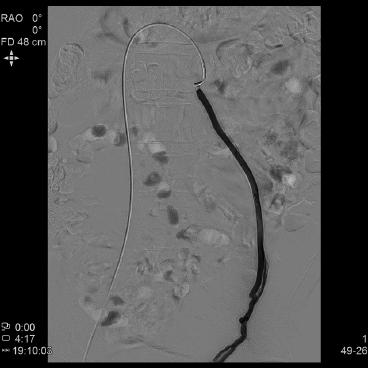

5.1.3.3血管造影(可选)

精索内静脉造影有助于减少高位结扎手术的失败率和分析手术失败原因。

5.2.3精索内静脉造影下的分度 根据精索内静脉造影的结果可分为3度1:①轻度:造影剂在精索内静脉内逆流长度达5cm;②中度:造影剂逆流至腰椎4~5水平;③重度:造影剂逆流至阴囊内。

6.3.4手术复发的判断与处理 精索静脉曲张患者无论采取何种外科治疗方式,都可能复发。判断精索静脉曲张是否复发的标准并不统一,欧美有些学者仍然以“触诊”作为诊断标准,仅在部分患者采用彩色多普勒超声检查。一般认为应综合术后6个月以后体格检查和彩色多普勒超声检查结果,当两者都达到临床型精索静脉曲张的诊断标准时,考虑存在复发;必要时可采用静脉造影术。复发性精索静脉曲张的治疗必须遵循精索静脉曲张的一般治疗原则,再次手术的指征需要符合手术适应证,根据患者及疾病的具体情况、手术史、医院条件、术者擅长,并在与患者和(或)家属充分沟通后,可以选择传统开放手术、显微手术、腹腔镜手术和精索内静脉造影同时行栓塞治疗等。